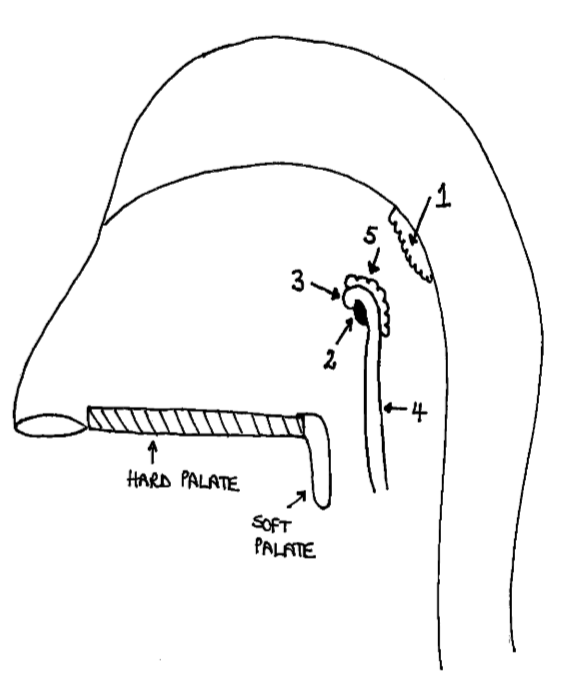

Which area of the head and neck do 1, 2, and 3 make?

pharynx

What region is 1?

nasopharynx

What region is 2?

oropharynx

What region is 3?

laryngopharynx

What is the horizontal dotted line?

pharyngeal isthmus

What is the vertical dotted line?

oropharyngeal isthmus

What is 1?

pharyngeal tonsil

What is 2?

pharyngeal opening of pharyngotympanic tube

What is 3?

tubal elevation

What is 4?

salpingopharyngeal fold

What is 5?

tubal tonsil